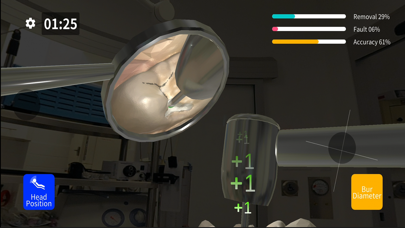

Скриншоты